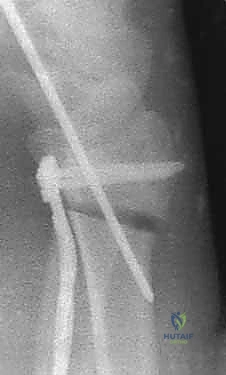

3. قص العظم التصحيحي (The Osteotomy)

بناءً على التخطيط الثلاثي الأبعاد المسبق، يستخدم الدكتور هطيف مناشير عظمية دقيقة جداً لعمل شق في العظم في نقطة التشوه الأصلية. يتم فتح العظم وتعديل زاويته واستعادة طوله الطبيعي.

5. التثبيت بصفائح التيتانيوم (Internal Fixation)

للحفاظ على الوضع الجديد والمثالي للعظم، يتم استخدام صفائح تيتانيوم متقدمة ذاتية الغلق (Volar Locking Plates). هذه الصفائح مصممة تشريحياً لتلائم شكل الكعبرة، وتوفر تثبيتاً قوياً جداً يسمح للمريض ببدء تحريك أصابعه في اليوم التالي للعملية.